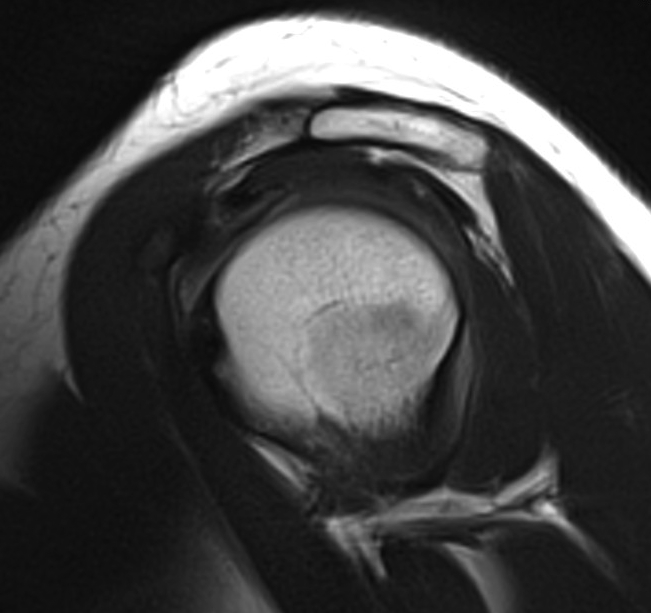

MRI

Mass lesions

Atrophy of T minor

Assess RC